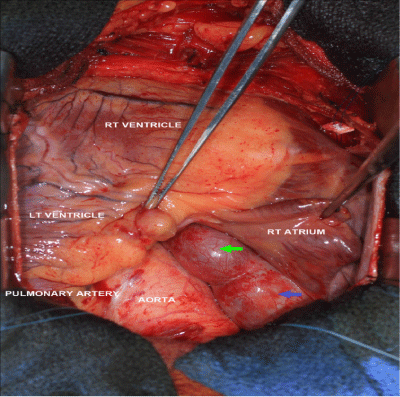

Figure 2 An intraoperative view. The blue arrow demonstrate the coronary artery fistula on the right side of the aorta and anteriorly.

On cardiopulmonary bypass, the right atrial appendage was opened and a 2cm wide orifice was found between the SVC and the tricuspid valve in the medial wall of the right atrium. There was also a separate orifice (0.4cm in diameter) into the medial right atrium, which appeared to be the fistulous tract from the right coronary artery. These orifices were oversewn and the right atriotomy was closed. The fistula was observed to pass posteriorly behind the aorta and pulmonary artery. The left main coronary artery was opened longitudinally near the base of the left atrial appendage. The 1cm orifice to the fistula was oversewn with a running 5-0 Prolene suture in a double layer. The left main coronary artery was then closed using a running 5-0 Prolene suture in a double layer anticipating a closure of 7mm in diameter. Antegrade cardioplegic solution was administered to test homeostasis of the anastomosis. The total cross-clamp time was 59minutes and total cardiopulmonary bypass time was 83minutes. The patient was separated from cardiopulmonary bypass without difficulty. Patient had an uneventfully post-operative course. A CTA thorax follow-up study 3-weeks later showed the post-surgical change of a thrombosed fistula.